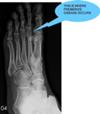

I would really appreciate any advice I can get, because I don't know where to turn. Locals are not very helpful, because they are just not good at judging a good doctor from a bad one. If you are better, the doctor was good; if not, he was bad. They seem to be unaware that doctors are not following any kind of standard routine in dealing with patients, and don't mind a three minute visit with a specialist with other patients standing around in the examination room breathing down your neck. By the way, I am 35 years old, 188cm, and 75 kg, so don't tell me to lose weight! I hope you don't mind if I add my latest x-ray. Perhaps you can see something the doctors don't.

That X-ray is too small for me to read. Could you send me the original scans. Did you digi them with your camera or are the digital X-rays? The lateral and oblique ankle and foot are usually more useful. But there is no substitute for a good physical exam. Is the fixation in the subtalar joint, or the cuboid... the metatarsals etc.

I'm afraid I don't see any signs of Freiberg's disease. I suspect, obviously without examining your foot this is very tentative, you have a case of metatarsalgia second to an old ankle sprain. You can see a bony spur forming in the calcano-cuboid joint, a sure sign of an old untreated injury.